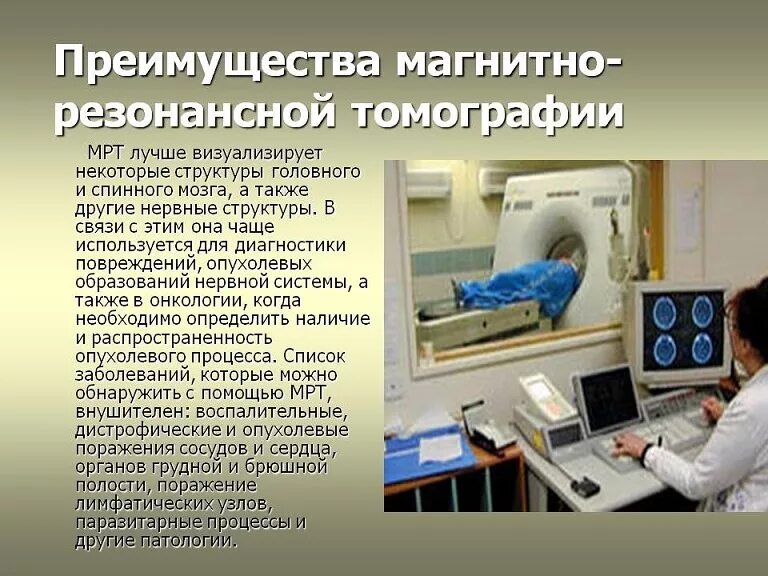

Опухоли головки поджелудочной железы классификация. Доброкачественная опухоль поджелудочной. Доброкачественная опухоль поджелудочной железы. Гистологическая классификация опухолей поджелудочной железы. Магнитно-резонансная томография. Исследования магнитно-резонансной томографии:. Обследование на томографе. Мрт.

Магнитно-резонансная томография. Исследования магнитно-резонансной томографии:. Обследование на томографе. Мрт. Онкологические заболевания. Злокачественная опухоль. Злокачественные новообразования. Опухолевые заболевания.